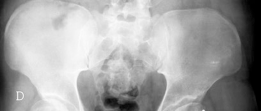

Standard radiographic series should include an anteroposterior pelvis, cross-table lateral, and false profile views of the affected hip. Functional views, such as maximum abduction and adduction radiographs, help quantify the degree of hinge abduction and the potential for concentric reduction.

Magnetic Resonance Imaging or Magnetic Resonance Arthrography is mandatory to assess the integrity of the articular cartilage, the viability of the subchondral bone, and the status of the acetabular labrum. Three-dimensional computed tomography reconstructions are highly recommended to map the exact topography of the deformity. Virtual surgical planning software can be utilized to simulate the osteotomy, calculate the wedge angle, and predict the final head-neck offset and sphericity.